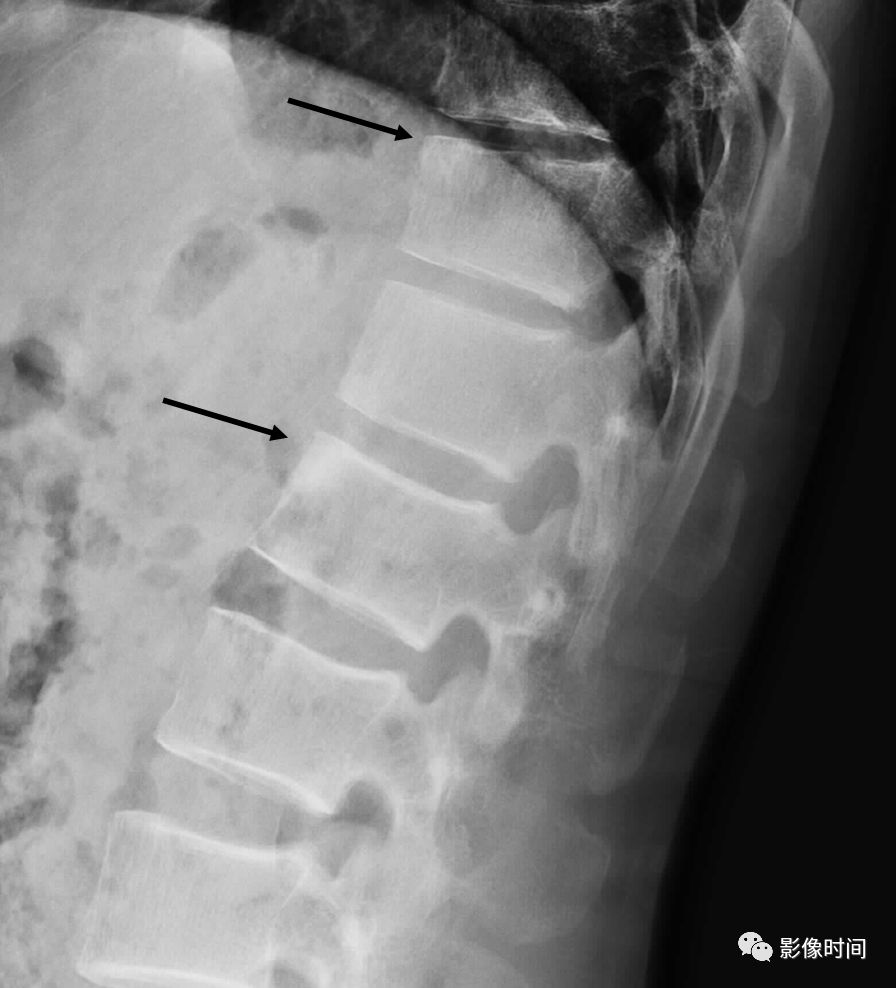

22亮角征

亮角征(shiny corner sign),又称 Romanus 病灶(Romanus lesion)

亮角征指的是在侧位片或者 CT、MRI 矢状位图像上,椎体的上角或者下角密度(或信号)增高(黑箭),「发亮」,故而得名。本征象主要见于血清阴性脊柱关节病(尤其是强直性脊柱炎)。在 X 线片上此征象的出现是由于于椎体角部炎症性侵蚀而导致的反应性骨质硬化。在磁共振上,活动性疾病表现为 T1WI 低,T2WI 压脂高信号,疾病进程后期则因为脂肪骨髓变性而呈现 T1WI、T2WI 双高信号。

典型病例

病例 1,53 岁男性,强直性脊柱炎。侧位 X 线片示部分椎体前上角密度增高,呈亮角征(黑箭)。

病例 2,男性,38 岁。强直性脊柱炎。A. 矢状位 T1WI 示胸腰段多发椎体角部信号增高(白箭),呈亮角征;B.STIR 序列亦呈稍高信号(白箭, 提示有活动性炎症)。

引用自:https://radiopaedia.org/articles/shiny-corner-sign-ankylosing-spondylitis